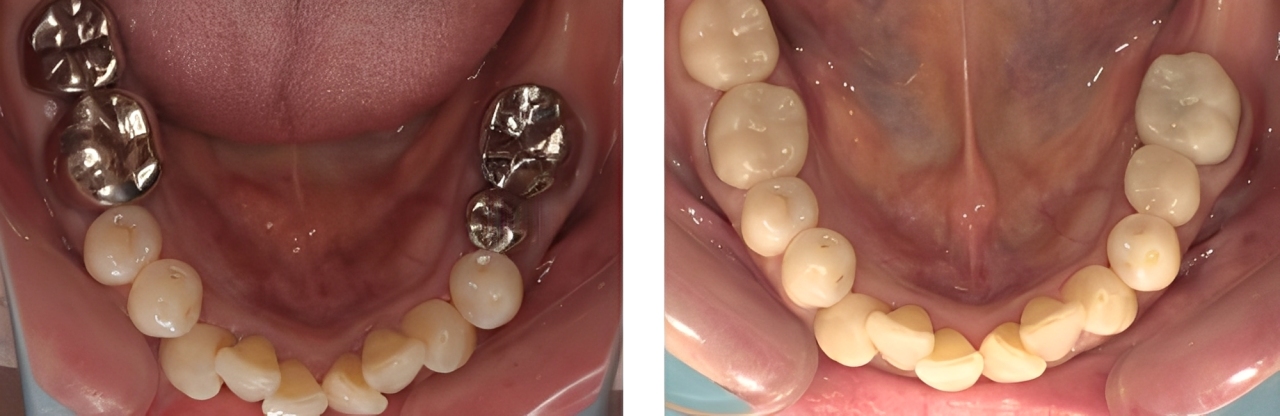

全顎保険治療

術前

術後

| 治療内容 | 全顎的に保険内で治療を行った |

|---|---|

| 治療期間・回数 | 約2.5年・約50回 |

| 治療期間・回数 | 約3年・約60回 |

| 費用 | 保険適用となります |